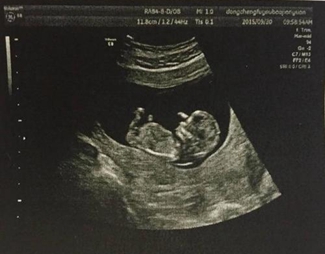

以灰階即亮度(brightness)模式形式來(lái)診斷疾病稱(chēng)“二維顯示”,因亮度第一個(gè)英文字母是B,故稱(chēng)B超,又稱(chēng)二維超聲或灰階超聲。

B型超聲是醫(yī)學(xué)影像學(xué)超聲的主要檢查方法,雖然超聲的發(fā)展突飛猛進(jìn),如內(nèi)鏡超聲、超聲造影、三維成像、彈性成像等等,都是在B型超聲基礎(chǔ)上發(fā)展起來(lái)的。因此,凡是進(jìn)行超聲工作的醫(yī)師及被檢查的患者,都應(yīng)該了解B型超聲的臨床醫(yī)學(xué)特點(diǎn)、檢查前準(zhǔn)備、檢查范圍及注意事項(xiàng)等等,以便更好地應(yīng)用它來(lái)為被檢查者服務(wù)服務(wù)。